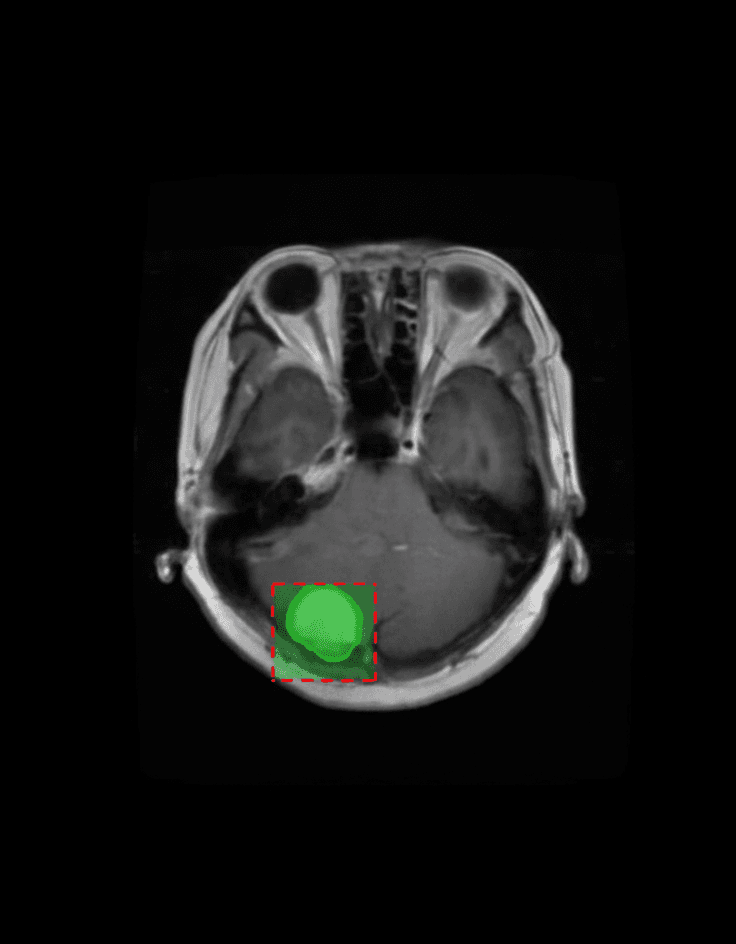

Our AI platform analyzes MRI scans using multi-sequence 3D deep learning models, automatically identifying and measuring tumor regions.

3D MRI Segmentation

Multi-sequence deep learning models for precise volumetric tumor segmentation

Deep Learning Analysis

Advanced neural networks trained on multi-center datasets for clinical-grade accuracy

Clinically Validated Results

Validated on multi-center datasets including BraTS and clinical pilot studies